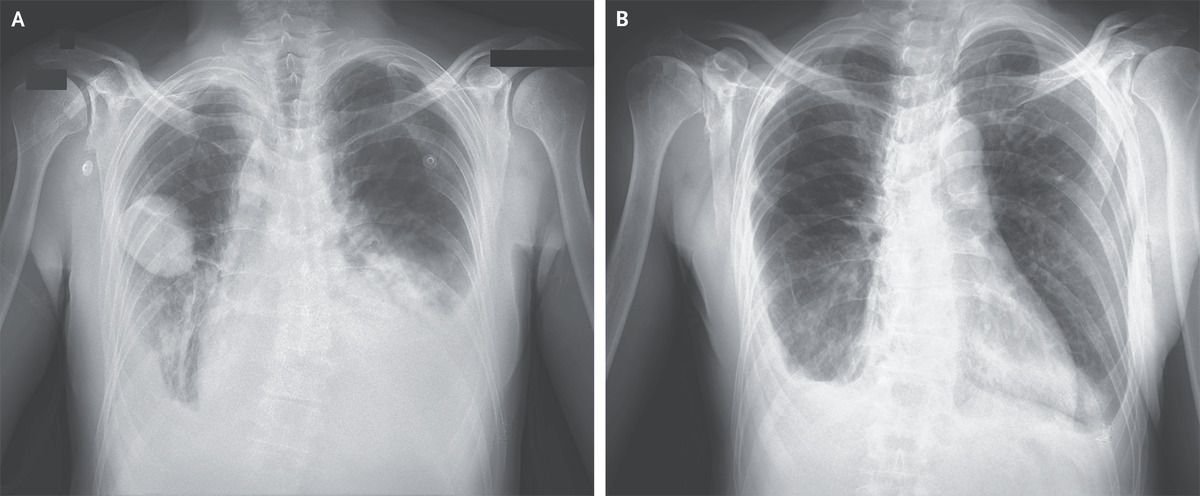

A 50-year-old man with a history of mitral-valve prolapse and of Hodgkin’s lymphoma 20 years earlier that was treated with chemotherapy and radiation therapy presented to the emergency department with a 5-day history of dyspnea. Physical examination showed jugular venous distention, diminished breath sounds at the lung bases, and a holosystolic murmur at the cardiac apex. A radiograph of the chest showed indistinct pulmonary vascularity, a dense retrocardiac opacity, and pleural effusions on both sides. A sharply demarcated, lenticular lesion was shown in the right middle lung field (Panel A, anterior–posterior view). An echocardiogram showed an ejection fraction of 45% and severe mitral regurgitation. Treatment with diuretics and vasodilators was initiated. A follow-up chest radiograph 3 days after presentation showed complete resolution of the right lung opacity, as well as reduced pulmonary edema (Panel B, posterior–anterior view). A diagnosis of phantom tumor of the lung was made. Phantom tumors of the lung, also known as vanishing tumors or pseudotumors, are loculated interlobar pleural effusions that occur most commonly in the minor fissure, as in this case. The resolution of phantom tumors with diuresis distinguishes them from true masses. Surgical coronary-artery revascularization and mitral-valve replacement were performed. At 1-month follow-up, the patient was doing well.